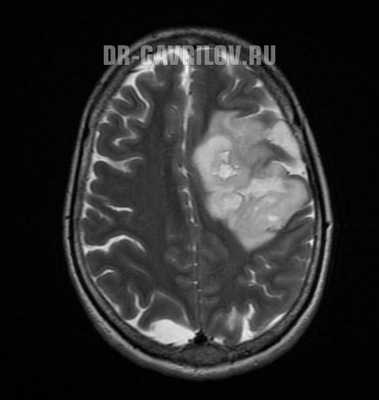

- Магнитно-резонансная томография - способна провести визуализацию опухоли в любом отделе головного мозга, выявить размер и пределы образования. В 98% случаях МРТ позволяет поставить точный диагноз. При необходимости процедура может проводиться с контрастом, что еще больше увеличивает информативность исследования.

- компьютерная (КТ) и магнитно-резонансная томография (МРТ) с контрастом - золотой стандарт при обследовании головного мозга, получаются высокоточные послойные изображения;